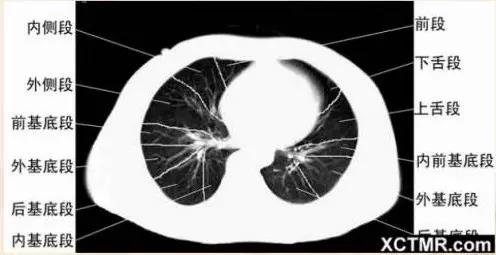

右基底支气管层面